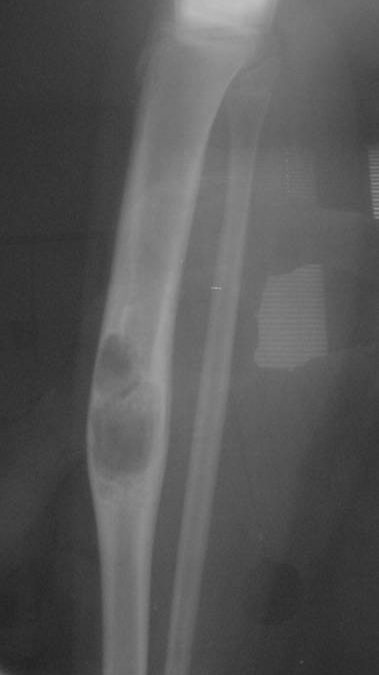

Aneurysmal Bone Cyst (ABC): Understanding This Benign but Aggressive Bone Lesion

An Aneurysmal Bone Cyst (ABC) is a benign but aggressive bone lesion that can cause swelling, pain, and fractures. Learn about its symptoms, diagnosis, and treatment options from the Tumor Surgery Network.